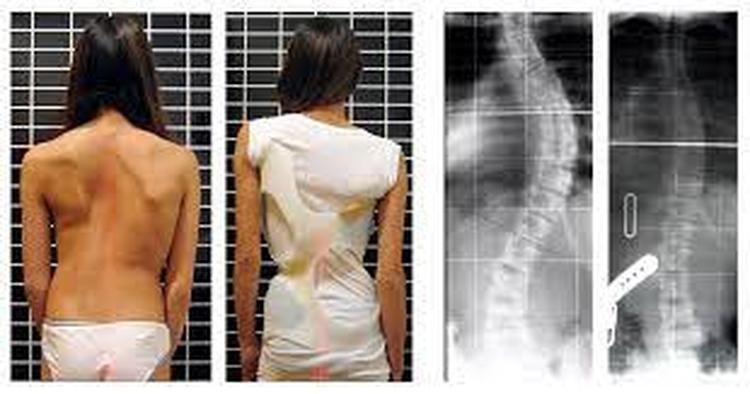

Para crianças menores, a recomendação mais comum é o uso do gesso corretivo para o desvio identificado, extremamente benéfico para a correção do problema. Mas, naquelas mais velhas e com uma curvatura superior à 35 graus, o colete é a medida mais vantajosa para evitar sua progressão. Em 70% dos casos, pode até mesmo impedir a necessidade de cirurgia para os pequenos que se encontram na fase mais importante de desenvolvimento infantil, que geralmente ocorre dos 10 aos 17 anos.

Geralmente, as escolioses idiopáticas diagnosticadas antes dos oito ou dez anos costumam evoluir para casos mais graves, uma vez que o potencial de crescimento da curvatura da coluna é maior. Já aquelas identificadas após essa idade, no período conhecido como o esporão de desenvolvimento do adolescente, tendem a desenvolver para um desvio do tronco para lateral ao longo do crescimento do paciente. Ambos podem acarretar diversos problemas de saúde quando não tratados corretamente, o que torna sua descoberta precoce um fator crucial para evitar estes cenários.